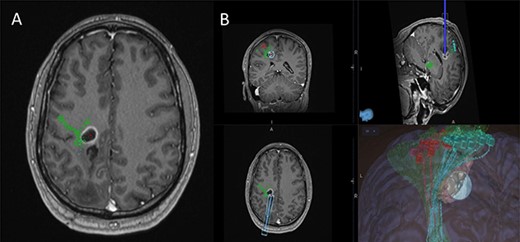

(A) Axial T1-weighted image with gadolinium showing the lesion with imposed DTI tractography of the CST; (B) planned trajectory for insertion of the tubular retractor guided by the preoperative integrated anatomical and functional motor mapping.

5-Aminolevulinic Acid (5-ALA) was given orally 2 h before the surgery. The least disruptive trajectory was selected taking into account the previous biopsy and the preoperative mapping information (Fig. 3). Under Stealth guidance, a skin incision was made overlying the planned craniotomy site. After the craniotomy, the dura was opened and a subdural strip of electrodes was placed over the primary motor cortex. Replicable motor responses from the hand muscles were obtained at 7 mA current intensity (Fig. 4). Motor evoked potentials (MEPs) were obtained continuously throughout the procedure. A transsulcal parafascicular approach was used. The sulcus was opened sharply under the microscope. At the depth of the sulcus, a preselected tubular retractor (NICO BrainPath 75 mm × 13 mm) was passed to the superficial surface of the lesion. While performing brain cannulation to the lesion, a monopolar probe (INOMED©) navigated with SureTrack (MEDTRONIC©) was used to perform continuous subcortical stimulation, train-of-five technique using high-frequency stimulation.

Two independent techniques were used to dissect the ipsilateral CST with StealthViz Software (MEDTRONIC©): region of interest (ROI) technique and TMS-seeded technique. In the first one, two ROIs were defined, precentral gyrus and midbrain at the level of the superior cerebellar peduncle, the anatomical streamlines going through both regions were selected. In the second technique, the positive nTMS responses for the upper and lower limb were selected independently as ROIs and the other ROI was in midbrain at the level of the superior cerebellar peduncle. Both dissections of the CST were used as they provided an anatomical and functional assessment of the tract. The tumour was delineated in the Cranial Software (MEDTRONIC©) and the preoperative cortical and subcortical mapping was integrated in a 3D model (Fig. 2).

Preoperative cortical and subcortical motor mapping was performed (Fig. 2). Diffusion tensor and spherical deconvolution tractography was used to delineate the anatomy of the CST bilaterally. Tensor-derived metrics were calculated for both CSTs. The fractional anisotropy and the hindrance-modulated orientational anisotropy of the left CST (tumour side) were lower. The axial, radial and mean diffusivities were higher in the left CST. Navigated TMS (NEXSTIM©; single pulse technique) was used to assess CST function. Abnormal interhemispheric RMT ratios (iRMTr) were found for both upper and lower limbs and an abnormal combined cortical excitability score (number of abnormal iRMTr)—2/2. This information suggested altered cortical excitability and microstructure of the CST on the side with the tumour.